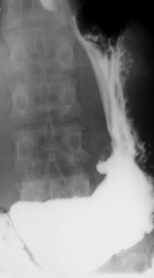

Achalazia cardiei